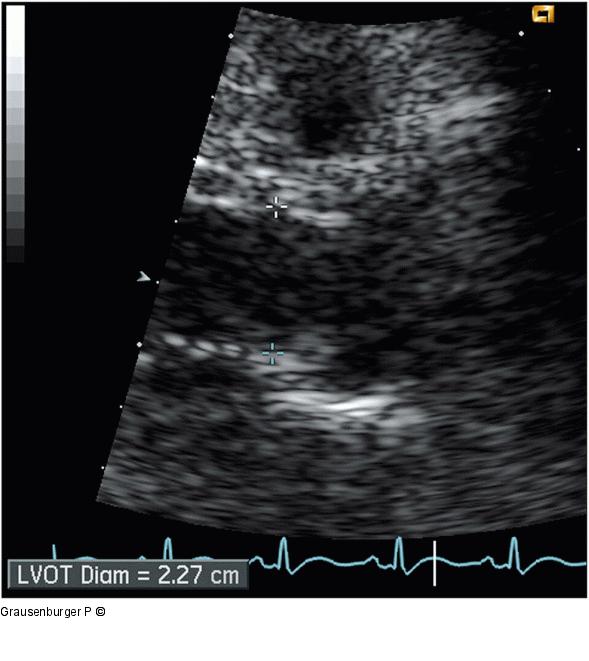

Abbildung 2: LV-Ausflußtrakt LV-Ausflußtrakt - Durchmesser (RES; von parasternal) |

LV-Ausflußtrakt - Durchmesser (RES; von parasternal) |